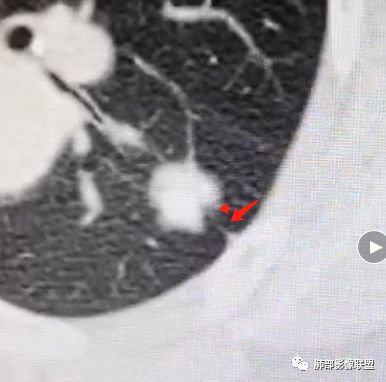

深分叶,脐凹征;边缘GGO边界清楚

就这几条就要考虑恶性

以往有专家总结这个体积缩小超过一半的,一般会考虑炎性病变,为什么,它渗出为主的吧,但是我们后面的后来就发现这个老前辈总结出来的理论有很多东西,就不合适。磨玻璃影的边界,这个边界如何?清不清楚,这个很重要,如果边界是很模糊的,不用考虑那是炎症。那你像这种边界非常清楚的又不密实的,那种高度警惕恶性的。